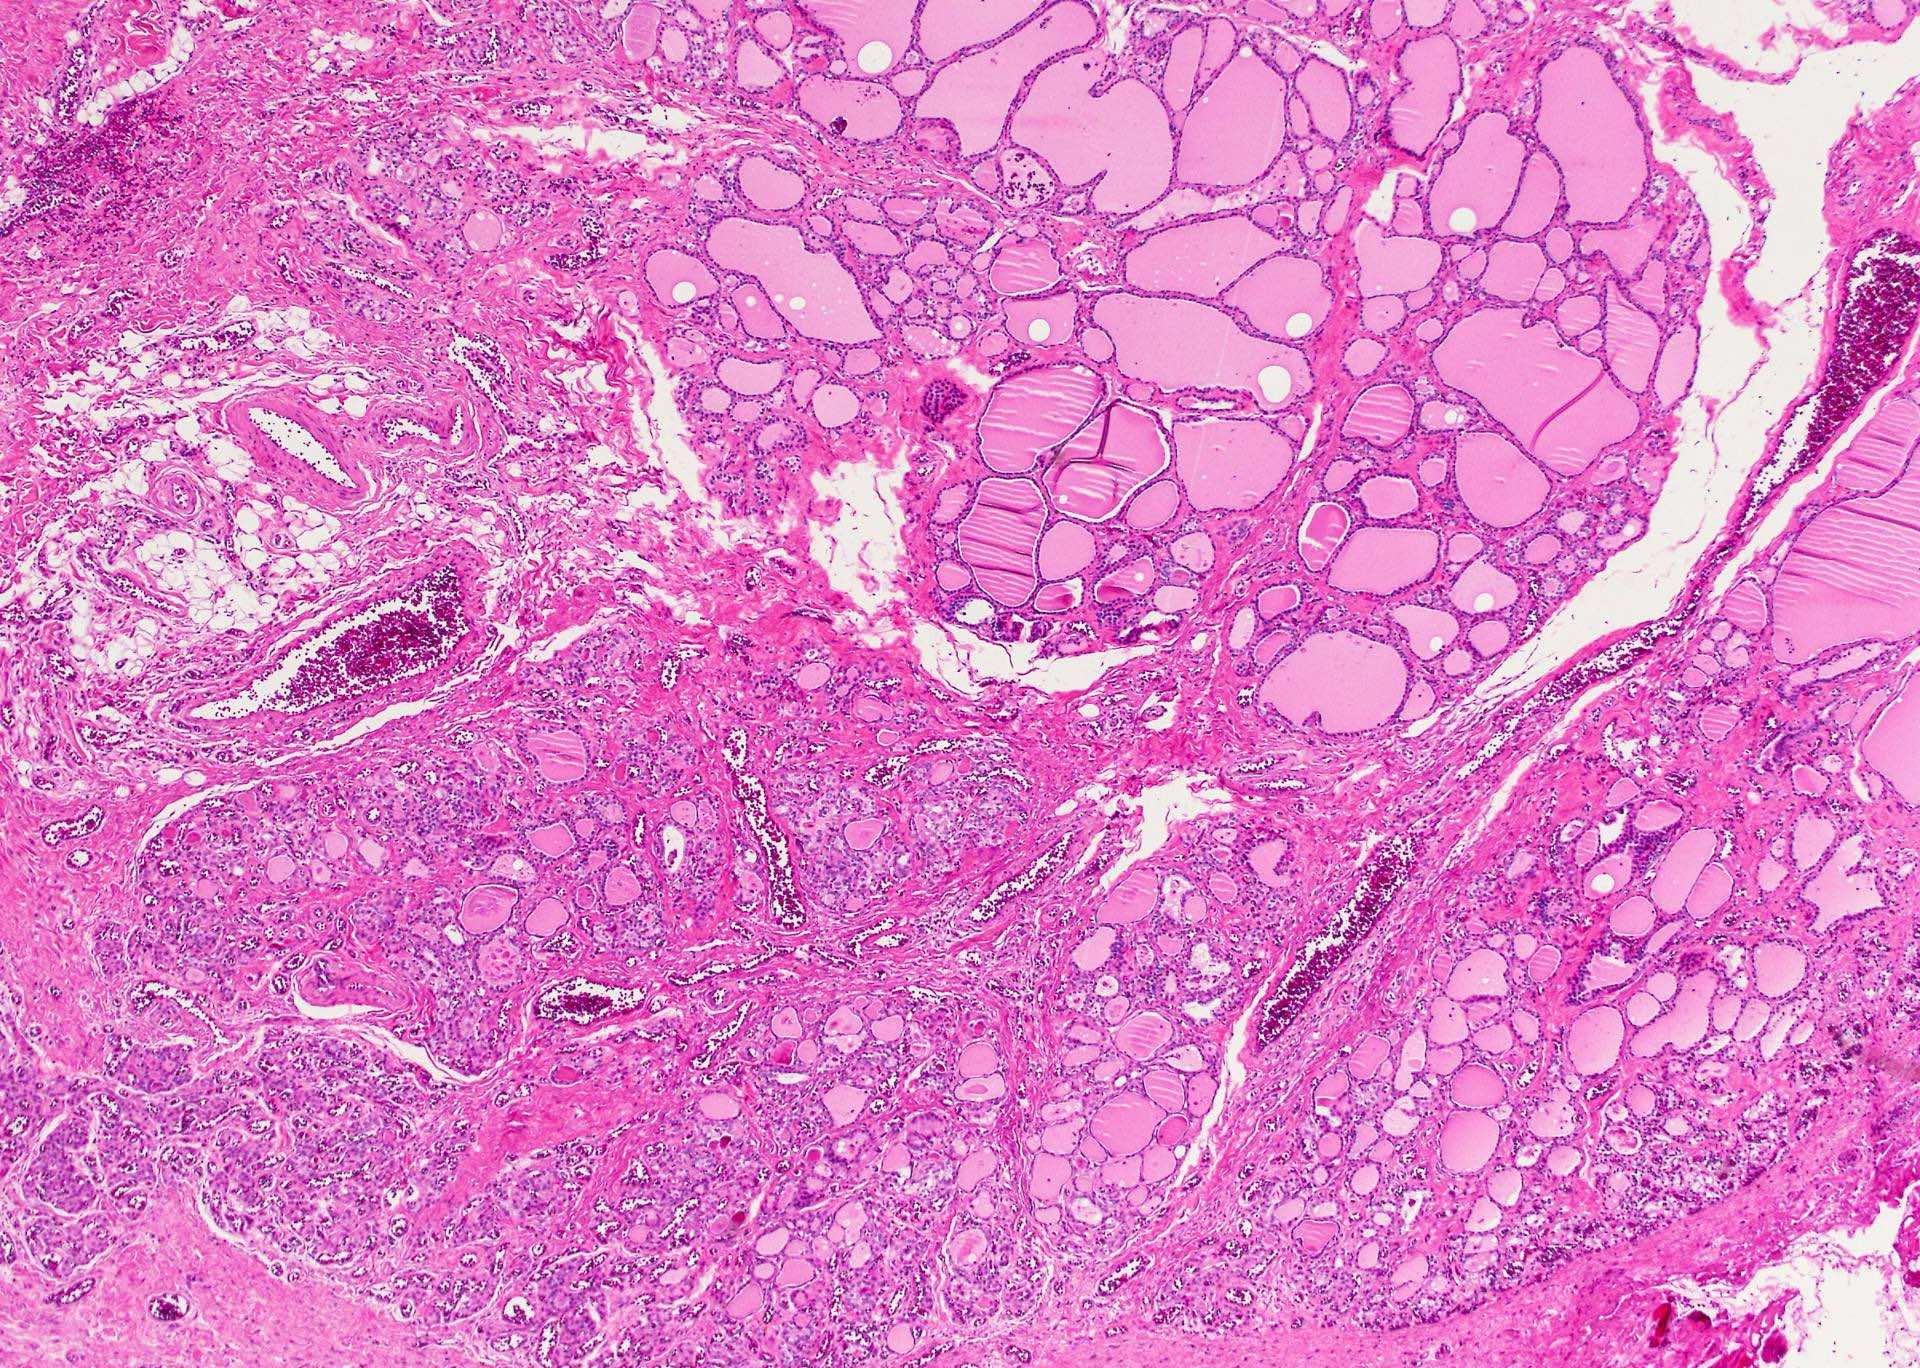

Microscopic (histologic) description

- Very often the cyst is denuded of epithelium, at least focally, which reflects epithelial damage by inflammation

- Secondary inflammation is common, especially in sinus tract (J Pediatr Surg 1984;19:506):

- Intense lymphocytic infiltration, rarely arranged into lymphoid follicles

- Admixture of neutrophils (if the cyst is infected)

- Granulation tissue and fibrosis

- Thyroid follicles in the cyst / duct wall:

- Found in 30% - 60%, with higher yield on serial sections

- Seen in small irregular groups

- Thyroid tissue often hidden by inflammation (Laryngoscope 2001;111:1002)

- Absence of thyroid tissue does not exclude the diagnosis of TGD cyst

- Mucous salivary-type glands can be found in the cyst wall, frequently in lingual and suprahyoid locations (Ann Otol Rhinol Laryngol 1996;105:996)

Microscopic (histologic) images

Contributed by Andrey Bychkov, M.D., Ph.D., Mark R. Wick, M.D. and AFIP